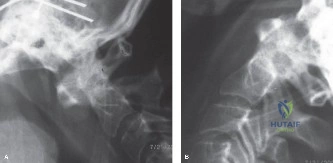

To contextualize the decision-making algorithm, consider the classic presentation of a middle-aged patient with multiple medical comorbidities. A paradigmatic case involves a 48-year-old obese female (Body Mass Index of 43) with poorly controlled diabetes mellitus who presents with severe, unrelenting low back pain, fevers, and chills. Advanced imaging, specifically magnetic resonance imaging (MRI), typically demonstrates discitis involving the L4–5 disc space with adjacent osteomyelitis of the L4 and L5 vertebral bodies. Crucially, in many early or medically responsive cases, there is an absence of epidural abscess formation, and standing radiographs reveal relatively normal sagittal and coronal alignment. When such a patient is neurologically intact—lacking saddle anesthesia, bowel/bladder incontinence, or upper motor neuron signs—the immediate clinical imperative shifts from urgent surgical decompression to aggressive pathogen identification and targeted antimicrobial therapy.

From a biomechanical perspective, the L4-L5 motion segment is subjected to some of the highest compressive and shear forces in the human body. The anterior column (comprising the anterior longitudinal ligament, anterior two-thirds of the vertebral body, and anterior annulus fibrosus) bears approximately 80% of the axial load in a healthy spine. When pyogenic osteomyelitis destroys the subchondral endplates and the intervening disc, the anterior column loses its structural integrity.

This structural compromise leads to pathological load transfer to the posterior elements (facets and pars interarticularis). As the anterior column collapses under the weight of the trunk, the spine inevitably drifts into a focal kyphotic deformity. This kyphosis not only alters global sagittal balance—requiring increased energy expenditure for standing and walking—but also narrows the neuroforamina and spinal canal, potentially compressing the exiting and traversing nerve roots. Therefore, any surgical intervention must not only eradicate the infectious nidus but also meticulously reconstruct the anterior weight-bearing column to restore physiological lordosis and biomechanical stability.

In addition to MRI, a fine-cut computed tomography (CT) scan is essential for evaluating bony destruction. CT allows the surgeon to assess bone stock for pedicle screw purchase and to template the size of the interbody cages required for anterior column reconstruction. Upright standing radiographs (if the patient can tolerate them) or full-length supine films are necessary to evaluate global spinal alignment and regional kyphosis.

Patient positioning depends entirely on the chosen surgical approach. For a posterior-only approach (e.g., transforaminal lumbar interbody fusion [TLIF] or posterior column osteotomy), the patient is positioned prone on a radiolucent Jackson table. Care must be taken to pad all bony prominences, allow the abdomen to hang free (to decrease venous pressure and epidural bleeding), and optimize cervical alignment. If an anterior approach is selected (e.g., anterior lumbar interbody fusion [ALIF] or lateral transpsoas approach), the patient is positioned supine or in the lateral decubitus position, respectively. Fluoroscopic localization prior to incision is mandatory to confirm the correct pathological level.